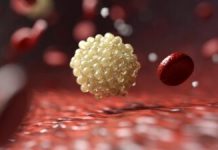

Un nou studiu clinic de fază II, condus de cercetătorii de la Memorial Sloan Kettering Cancer Center și Weill Cornell Medical College, indică faptul că tratamentul unui subset de pacienți cu cancer pancreatic, ghidat de biomarkerii specifici, ar putea extinde semnificativ durata de supraviețuire. Studiul, publicat în revista Nature Medicine, subliniază potențialul în creștere al imunoterapiei de precizie în lupta împotriva uneia dintre cele mai letale forme de cancer.

Trialul POLAR (Pembrolizumab și OLApaRib) s-a concentrat pe pacienții cu cancer pancreatic metastatic, ale căror tumori prezentau deficiențe de recombinare omoloagă (HRD) – o caracteristică genetică asociată cu repararea defectuoasă a ADN-ului. HRD este adesea cauzată de mutații genetice în genele BRCA1, BRCA2 sau PALB2 și s-a demonstrat că aceasta crește sensibilitatea la chimioterapia pe bază de platină și inhibitorii PARP, o clasă de medicamente care perturbă și mai mult repararea ADN-ului.

În cadrul trialului POLAR, 63 de pacienți al căror tratament stabilizase boala după chimioterapia cu platină au primit o combinație de olaparib, un inhibitor PARP, și pembrolizumab, un inhibitor al punctelor de control imunitar, ca terapie de întreținere. Participanții au fost clasificați în trei grupuri, pe baza biologiei tumorii: cei cu mutații HRD de bază (cohorta A), cei cu mutații înrudite, dar mai puțin definite (cohorta B), și cei fără HRD, dar cu boală sensibilă la platină (cohorta C).

Deși trialul nu și-a atins obiectivele primare, rezultatele au arătat un semnal clinic semnificativ în grupul HRD. Pacienții din cohorta A au avut o supraviețuire medie fără progresie de 8.3 luni și o supraviețuire totală medie de 28 de luni, cifre considerabil mai mari decât media pentru cancerul pancreatic avansat. Notabil este că 44% dintre acești pacienți erau încă în viață după trei ani, un procentaj neobișnuit de mare pentru această boală.

Rata de răspuns a variat în funcție de subgrupul genetic. Tumorile cu mutații HRD de bază au avut o rată de răspuns obiectiv de 35%, comparativ cu doar 8% și 14% în cohortele B și C, respectiv. Includerea pacienților care au avut anterior răspunsuri profunde la chimioterapie a crescut rata de răspuns efectivă în grupul HRD la peste 50%, indicând că această populație este deosebit de sensibilă la abordarea combinată.

Studiul a inclus de asemenea analize extinse ale biomarkerilor pentru a determina de ce unii pacienți au beneficiat mai mult decât alții. Tumorile din grupul HRD au arătat niveluri mai ridicate de instabilitate genomică, inclusiv un număr crescut de mutații cunoscute ca inserții și deleții de cadre. Aceste mutații pot genera neoantigene, făcând celulele canceroase mai vizibile pentru sistemul imunitar.

Consistent cu acest lucru, tumorile HRD au prezentat și o infiltrare mai mare a celulelor imune, în special limfocitele tumorale infiltrative. Pacienții cu o prezență mai mare a celulelor imune și nivele mai scăzute de ADN tumoral circulant au avut șanse mai mari să experimenteze un control durabil al bolii, în unele cazuri durând mai mult de trei ani.

Cu toate acestea, relația dintre genetica tumorii și răspunsul imun nu a fost simplă. Deși tumorile HRD tind să fie mai imunogenice, nu toate au arătat răspunsuri imune puternice.